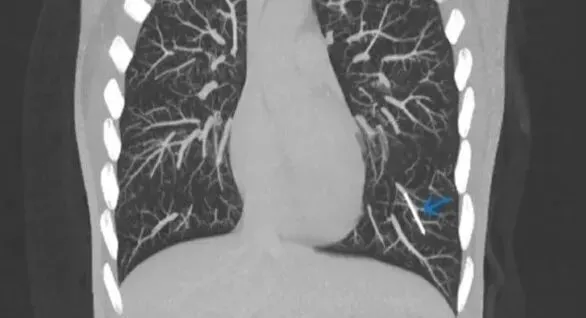

通过CT检查,医生在一位英国女性的肺里发现了意想不到的东西:一根失踪多年的避孕植入物[8]。

用于避孕的皮下埋植物通常很安全,但在罕见的情况下,它也有可能在人体内游走,甚至到达肺部。图中蓝色箭头标记的小棒就是进入肺部动脉的“流浪植入物”。 | Kareem et al.

这种植入物是火柴大小的弹性棒状物,它原本应该埋植在使用者手臂的皮下,通过缓慢释放孕激素发挥避孕功能。皮下埋植是效果最可靠的避孕手段之一,但在罕见的情况下,植入物有可能会在体内移位。

在这位女患者体内,植入物卡在了左下肺的一段动脉里。它应该是首先进入了手臂的静脉,然后顺着血液回流来到心脏,最后到达了肺部。医生推测,这种情况可能与植入时操作不当有关。